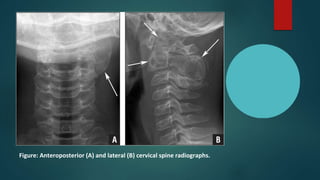

Figure: Anteroposterior (A) and lateral (B) cervical spine radiographs.

X-ray cervical spine showing destruction of the C3 vertebral body and its posterior

elements.

Figure: Anteroposterior (A)and lateral (B) cervical spine radiographs.

X-ray cervical spineshowing destruction of the C3 vertebral body and its posterior elements.

• ABC is normally placed in the metaphysis and appears as a

osteolytic lesion. The periosteum is elevated and the cortex is

eroded to a thin margin.

• The expansile nature of the lesion is often reflected by a

"blown-out" or "soap bubble" appearance.

• The lesion rarely penetrates the articular surface or growth

plate.